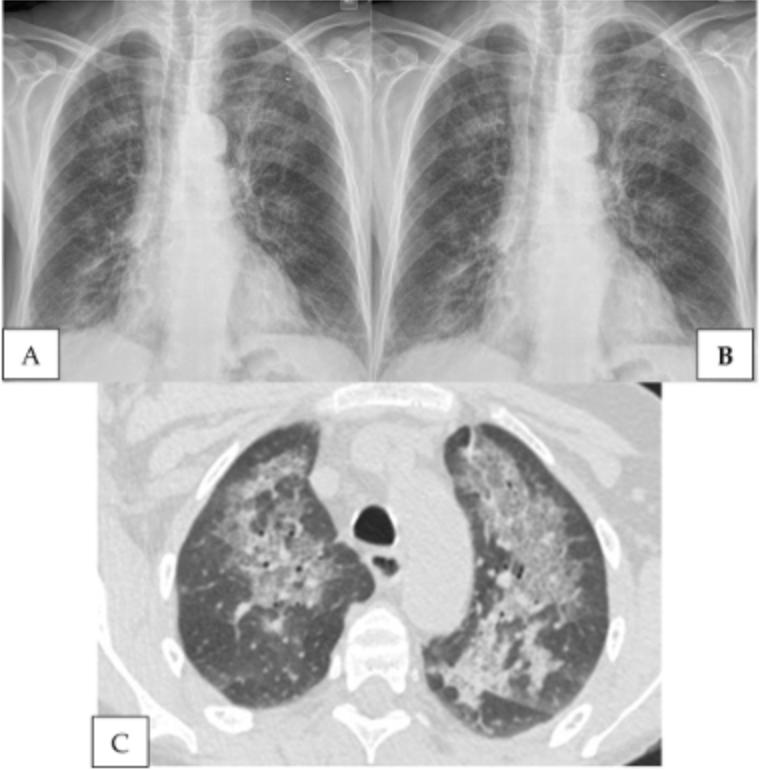

Answer: B) Pneumocystis Jirovecii